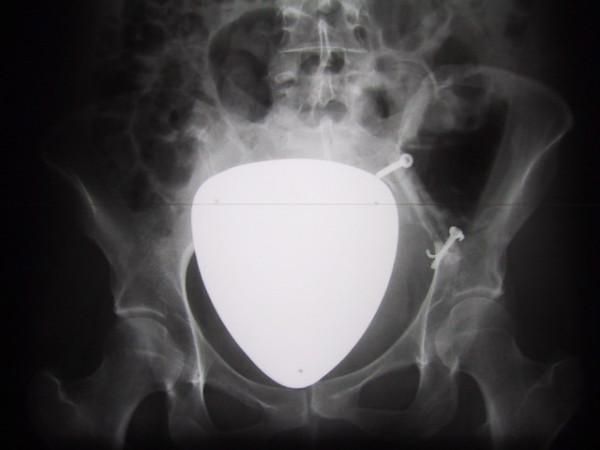

A 34-year-old female presented with BFH at a rare anatomical location on both sides of the os ilium which was larger than earlier reported BFH of the bone. Surgical resection was performed successfully including resection of the inner pelvic ring and reconstruction of the linea terminalis using a non-vascularized fibular autograft. At 18 months after tumor resection and reconstruction of the pelvic ring, with interposition of a free vascularized fibula graft patient has an excellent clinical oncological and functional outcome.

一名34岁女性在双侧髂骨罕见的解剖位置出现BFH,其尺寸大于先前报道的骨源性BFH。成功实施了手术切除,包括切除骨盆内环并使用非血管化腓骨自体移植重建耻骨梳韧带。在肿瘤切除及骨盆环重建18个月后,通过置入游离血管化腓骨移植,患者获得了出色的临床肿瘤学及功能预后。